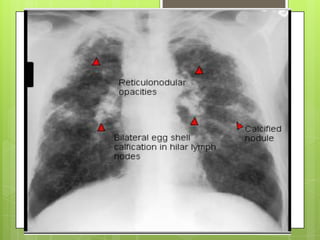

 Datos clínicos no son específicos.

 Formas leves no causan síntomas

 En etapas avanzadas: tos (primero) y disnea

Rx tórax:

 Formas simples nódulos redondeados densos

de 1.5-10 mm en campos pulmonares

superiores

 Formas complicadas: lesiones > 10 mm en uno

a dos tercios del pulmón. Calcificación de

ganglios en “cascara de huevo” ocurre en 5%

DIAGNÓSTICO

 Exposición laboral >5 años

 Radiografía con imágenes compatibles